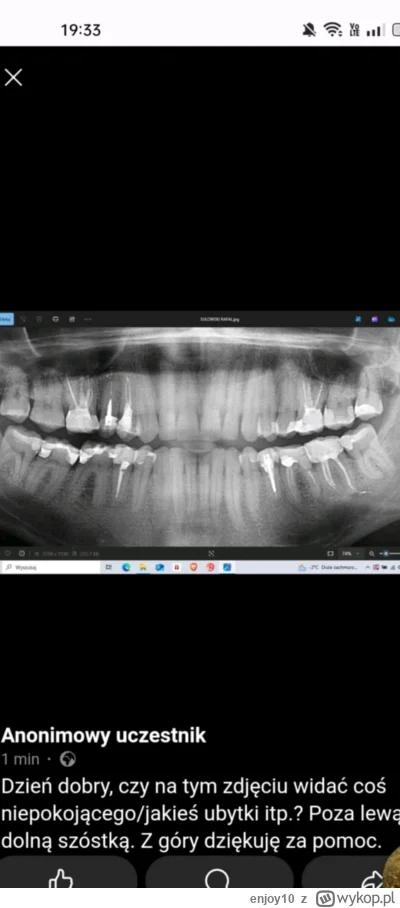

opis odnośnika czy tego zęba jest sens ratować? jestem umówiony na wyrwanie i zastanawiam się czy nie odwołać i nie próbować go ratować. Ponowne kanalowe itp. różne są opinie dentystów

#stomatologia #dentysta #zeby

@ali_baba: różne mam opinie ogólnie, ostatnio stomatolog w Lublinie mi powiedziała, że dla niej to jest problem dziąsłowy, stąd pulsowanie, ból. I faktycznie po antybiotyku w strzykawce było lepiej. I żeby wymienić wypełnienie i zostawić tak jak jest. I że z tymi korzeniami z implantem nie będzie tak hop siup. Zresztą nie chcę implantu. Teraz się zastanawiam czy go leczyć ponownie kanałowo czy tylko wymienić wypełnienie.

@ali_baba: sam nie wiem już co o tym myśleć, bo wypowiadało się już na temat zęba kilku dentystów. I było kilka opinii, żeby zostawić tak jak jest, a że pulsuje to problem z dziąsłem a nie stricte związany z kanałami. Były też opinie, żeby leczyć (klztownie) lub wyrywać.

@ali_baba: a według Ciebie co powoduje ból/pulsowanie? To zaciemnienie? Czy to jakiś stan zapalny dziąseł?